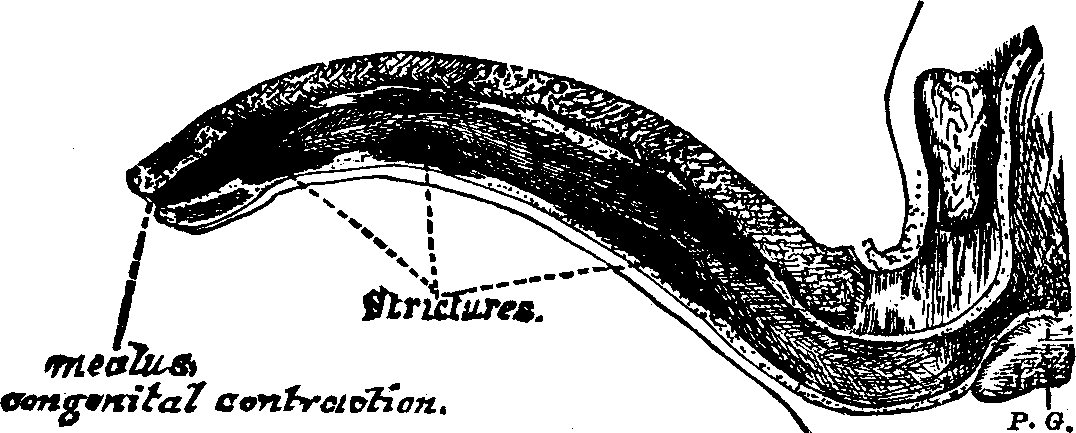

In the obstructive variety of dysmenorrhea, some organic impediment hinders the exit of the menstrual blood from the uterus, which, consequently, becomes distended and painful. The pain may be constant, but is most acute when the uterus makes spasmodic efforts to discharge the menstrual blood. If these efforts prove successful, there is an interval of relief. Flexion or version of the womb may produce partial occlusion of the canal of the neck of the uterus, thus preventing the free flow of the menstrual fluid through it. Tumors located in the body or neck of the uterus often cause obstruction to the free discharge of the menses. Imperforate hymen and vaginal stricture also sometimes cause obstruction and give rise to painful menstruation. As these several abnormal conditions and diseases will be treated of elsewhere in this volume, we omit their further consideration here.

Partial adhesion of the walls of the neck of the womb may result from inflammation of the mucous lining, and prevent a free and easy exit of the menstrual fluid. In many cases, the contracted and narrowed condition of the canal of the cervix seems to be a congenital deformity, for we can trace it to no perceptible cause. It is also true that contraction and partial, or even complete, stricture of the cervix, or neck of the womb, often results from the improper application of strong caustics to this passage by incompetent and ignorant surgeons. Every person has observed the contraction of tissue caused by a severe burn, which often produces such a distortion of the injured part as to disfigure the body for life. A similar result is produced when the neck of the womb is burned with strong caustics. The tissues are destroyed, and, as the parts heal, the deeper-seated tissues firmly contract, forming a hard, unyielding cicatrix, thus constricting the [pg 695]neck of the womb, through which the menses pass into the vagina.

Treatment. From the nature of this malady, it will readily be seen that no medical treatment can effect a radical cure. We must therefore resort to surgery. In a small proportion of cases, the stricture may be cured by repeated dilations of the constricted part of the cervical canal. This may be accomplished by using a very smooth probe which is fine at the point, but increases in size, so that its introduction will widen and expand the orifice and canal. The stricture may be overcome in many cases by using different sized probes. In some instances, we have employed the uterine dilator, represented by Fig. 3. We have also introduced sea-tangle and sponge tents into the neck of the womb, and allowed them to remain until they expanded by absorbing moisture from the surrounding tissues. The latter process is simple, and in many cases preferable. By means of a speculum (see Figs. 15 and 16), the mouth of the womb is brought into view, and the surgeon seizes a small tent with a pair of forceps and gently presses it into the neck of the womb, where it is left to expand and thus dilate the passage. If there seems to be a persistent disposition of the circular fibers of the cervix to contract, and thus close the canal, a surgical operation will be necessary to insure permanent relief. In performing this operation, we use a cutting instrument called the hysterotome (see Figs. 4 and 5). By the use of this instrument, the cervical canal is enlarged by an incision on either side. The operation is but slightly painful, and, in the hands of a competent surgeon, is perfectly safe. We have operated in a very large number of cases and have never known any alarming or dangerous symptoms to result. After the incision, a small roll of cotton, thoroughly saturated with glycerine, is applied to the incised parts, and a larger roll is introduced into the vagina. The second day after the operation, the cotton is removed, the edges of the wound separated by a uterine sound or probe, and a cotton tent introduced into the cervix, and allowed to remain, so that it will expand and thus open the wound to its full extent. This treatment must be thoroughly applied, and repeated every alternate day, until the incised parts are perfectly healed.

Treatment. An extensive observation and experience in the treatment of sterility, convinces us that, in the majority of cases, barrenness is due to some form of disease which can be easily remedied. If the passages through the neck of the uterus be closed or contracted, and this is the most frequent cause of sterility, a very delicate surgical operation, which causes little if any pain or inconvenience to the patient, will remove the impediment to fertility. In many of these cases, we have succeeded in removing the contraction and stricture of the neck of the womb by dilatation. When the vaginal walls are so firmly united as to prevent copulation, a surgical operation may be necessary to overcome their adhesion. When the hymen obstructs the vaginal orifice, a similar operation may be necessary to divide it. Vaginismus, which will be treated elsewhere, sometimes causes sterility.